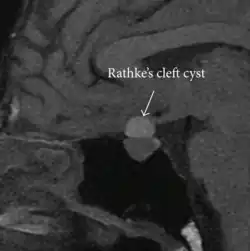

| Rathke's cleft cyst in a 53-year-old man with a pituitary adenoma and acromegaly |

A Rathke's cleft cyst is a benign growth on the pituitary gland in the brain, specifically a mucin-filled[1] cyst in the posterior portion of the anterior pituitary gland.[2][3] It occurs when the Rathke's pouch does not develop properly and ranges in size from 2 to 40 mm in diameter.[3]